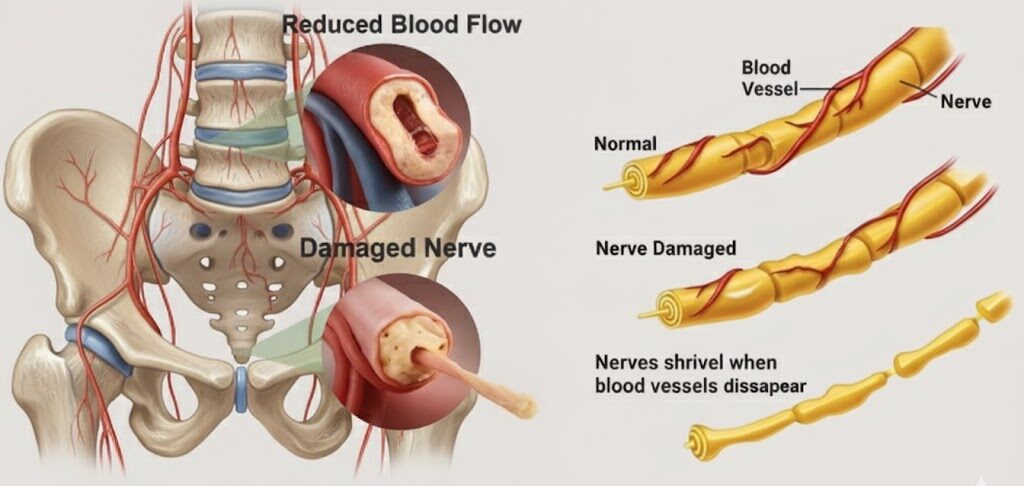

Your Pelvic Region Is Packed with Over 200,000 Nerve Endings

Nerve endings are tiny messengers. They detect touch, pressure, temperature, arousal — and instantly report back to your brain.

But Over Time, Nerve Damage Builds Up

Years of stress, aging, poor circulation, inflammation, lifestyle habits, even environmental toxins — all take a toll on the sexual nerves responsible for erections.

It often starts small: reduced sensitivity, delayed responsiveness, or that “numb” feeling that wasn’t there before.

Then it worsens into inconsistent erections, softer erections, or losing firmness midway.

Eventually, the nerves may degrade so much that they fail to transmit arousal signals at all — resulting in full erectile dysfunction.

Once that happens, even strong desire or mental arousal doesn’t translate into a physical response.

Because if the nerves can’t feel or transmit stimulation… the body simply doesn’t react.

Nerve tissue heals slower than almost anything else in your body.

At best, nerves regenerate at about one inch per month.

Given the length and complexity of the pelvic nerve pathways… natural recovery without targeted help can take years — sometimes decades.